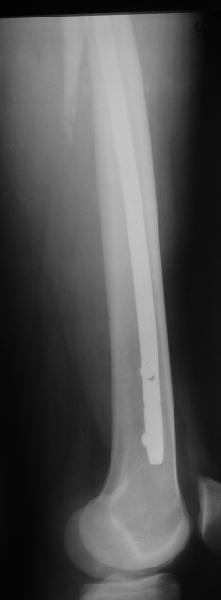

Второй случай тоже репозиция из малого доступа, больному 19 лет, множественные огнестрельные повреждениия конечностей, живота и черепа, правая конечность холодная, без пульсации. Ортопедический диагноз: огнестрельный перелом правого бедра. При срочной ангиографии повреждения сосудов не подтвердилось, конечность из-за ургентности состояния больного зафиксирована временным наружным фиксатором и больной оставлен на операционном столе для срочной лапаротомии хирургической службой.

Больной долго оставался нестабильным, только на 14 день удалось заменить на антеградный интромедуллярный штифт TFN (trochanteric femoral nail) SmithNephew. После неудачной попытки закрытой репозиции, несмотря на использование "joystick", проксимальный стержень от

наружного фиксатора, (перелом начал срастаться) репозицию провели из малого доступа, затем остальные этапы операции.

Случай был представлен из-за того, что больного оперировали после наружной фиксации и был риск инфекцирования через места проведения стержней (на снимках), прошло больше 3 месяцев, выписан из амбулаторной службы из-за отсутсвия надобности дальнейшего наблюдения.